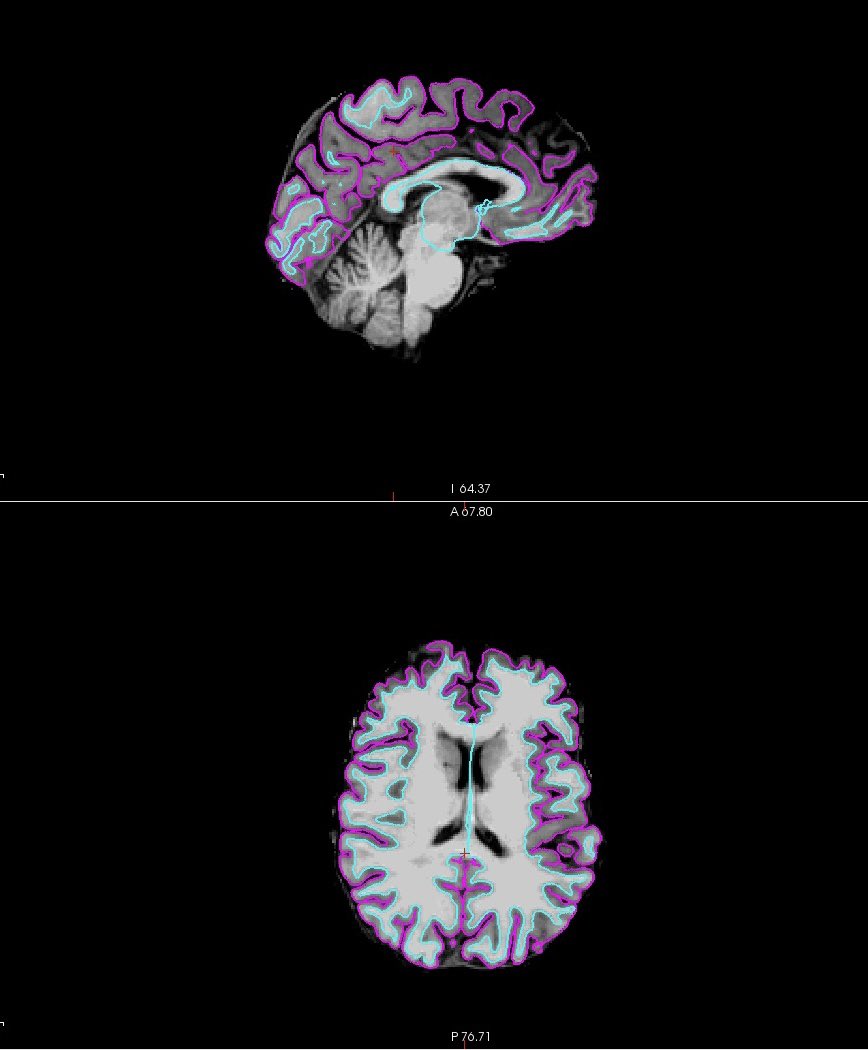

Excitement today after some pretty perfect FreeSurfer recon data 🧠 Thanks Brooklyn for all your help!